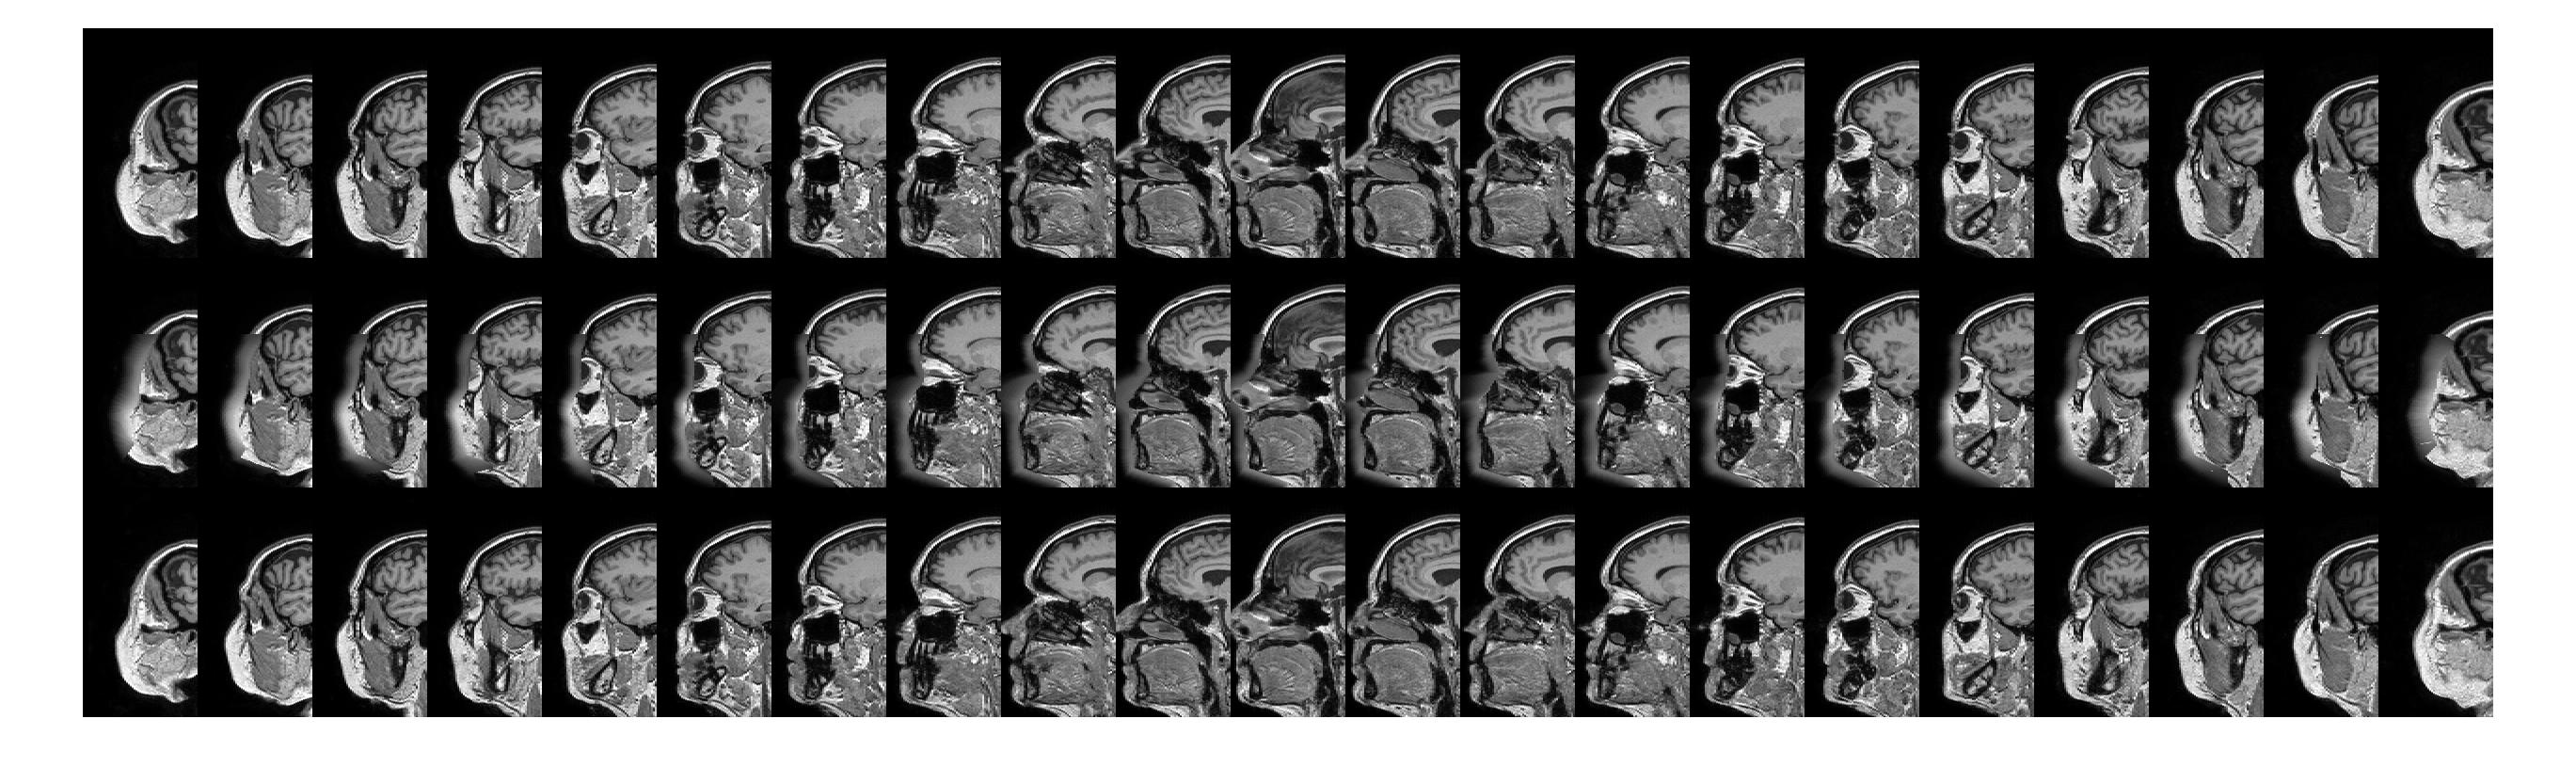

Refer to caption

Fig. 3: Example results for all 21 slices of a test subject from the Guy’s Hospital data. Good results are achieved for most slices. Top row: original image, middle row: face-blurred image, bottom row: reconstructed image.

Our approach managed to convincingly reconstruct the facial features for the face-blurred images (see Figure 1). The results for the single dataset experiment were particularly consistent (see Figure 3). Results were also positive for the full experiment, but showing a slight dependence of reconstruction quality on acquisition site. Qualitatively the images from Guy’s Hospital attained the best results, followed by those of Hammersmith Hospital, and finally those of the Institute of Psychiatry.